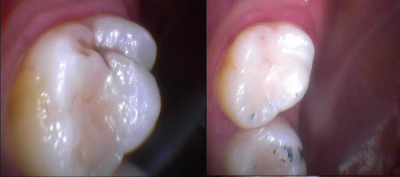

Gallery

Galeria